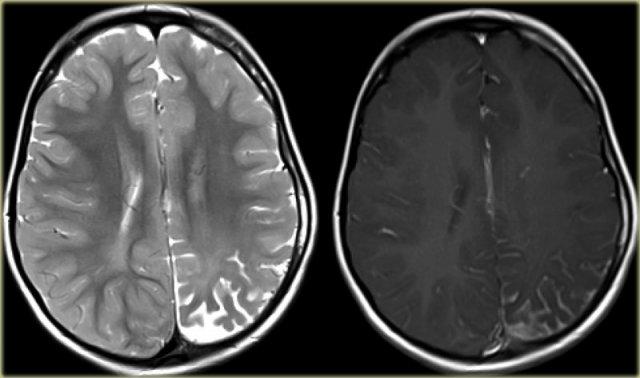

Ảnh chuỗi xung T1W, T2W và FLAIR mặt phẳng axial của bệnh nhân nam 15 tuổi bị động kinh.

Lưu ý hình ảnh dày và tăng tín hiệu vỏ não hồi trán trên bên trái.

Ảnh FLAIR cũng cho thấy tăng tín hiệu ở chất trắng dưới vỏ.

Các dấu hiệu này điển hình cho loạn sản vỏ não khu trú.